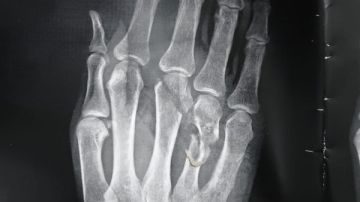

ووأوضح الديب، بأنه بفحص ومناظرة الحالة، تبين أن المريض يعاني من بتر جزئي باليد اليمنى مع قطع كامل بالأوتار الباسطة لليد والأصابع وتهتك بالأعصاب وفقد جزء من الجلد، بالإضافة إلى كسور بالمشطية الثانية والثالثة والرابعة باليد اليمنى.

وتابع مدير مستشفى قنا العام، وعلى الفور تم حجز الحالة وإجراء الفحوصات اللازمة وتجهيزها لدخول غرفة العمليات حيث تم إجراء تدخل جراحي دقيق لإصلاح الأوتار المقطوعة وتثبيت الكسور والتعامل مع الإصابات المصاحبة، مع إعطاء الدم والعلاج اللازم للمريض.